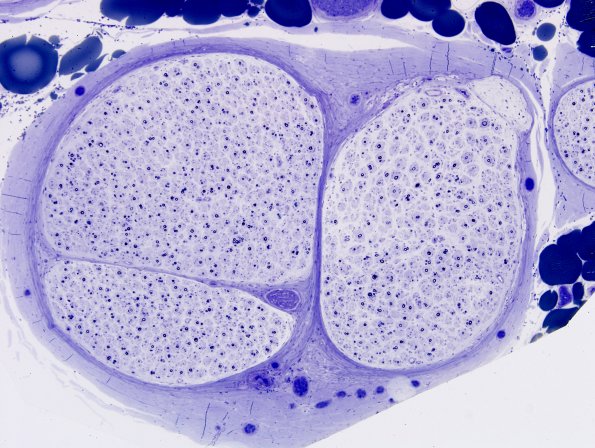

20B2 GBS, Chronic (Case 20)

A plastic image showing expected onion-bulb formation. (Plastic sections)